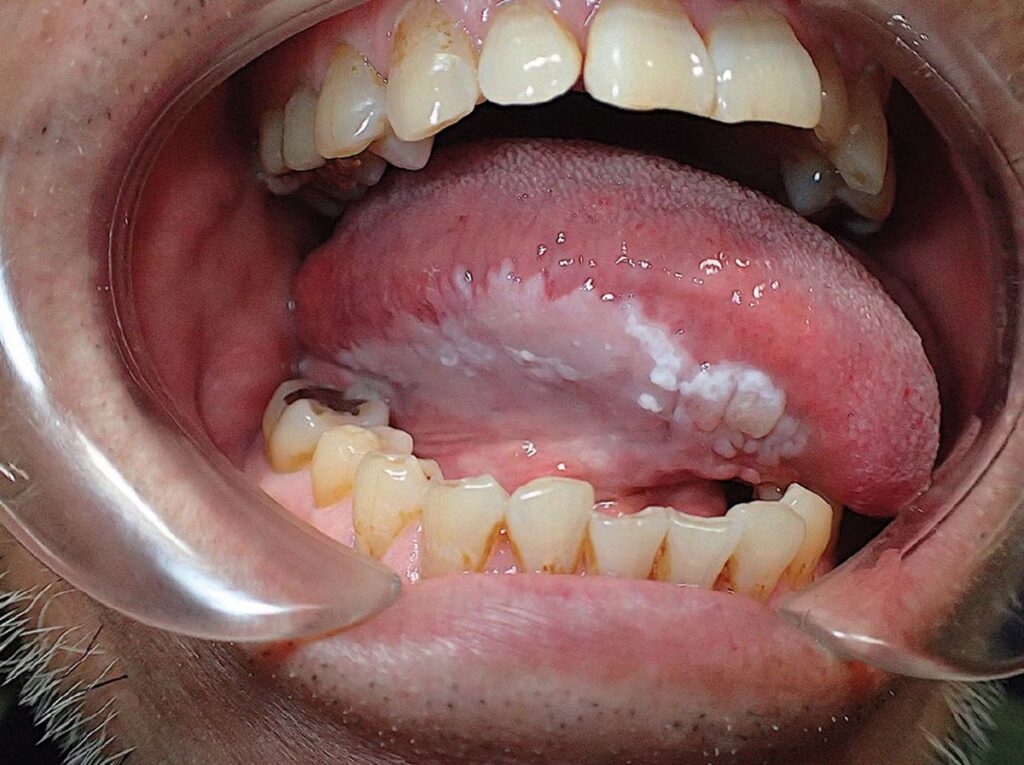

3. Leukoplakia

Removal and Risk Elimination

Leukoplakia is the most serious cause of white gum patches and requires the most direct approach. Because it is classified as potentially precancerous, monitoring alone is never sufficient.